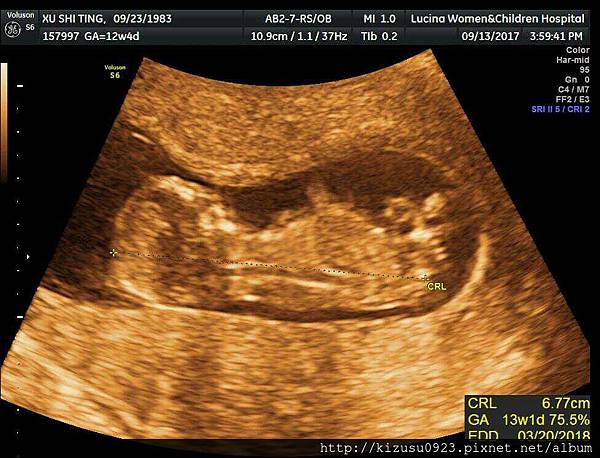

四季台安方俊能醫生 懷孕12週又4天 胎兒性別已揭曉 胎盤位置有點低 提早使用托腹帶 雪花台湾